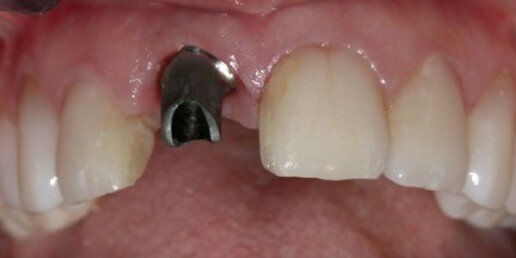

Caso 2

Impianto post-estrattivo immediato e innesto connettivale.

Prima

Dopo